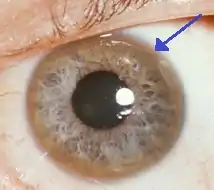

- Eyes: Kayser–Fleischer rings (KF rings) may be visible in the cornea of the eyes, either directly or on slit lamp examination as deposits of copper form a ring around the cornea. This is due to copper deposition in Descemet's membrane. These rings can be either dark brown, golden, or reddish-green, are 1 to 3 mm wide, and appear at the corneal limbus. They do not occur in all people with Wilson's disease and may be seen in people with chronic cholestasis.[10][11] Wilson's disease is also associated with sunflower cataracts exhibited by brown or green pigmentation of the anterior and posterior lens capsule.[12] Neither causes significant visual loss.[5] KF rings occur in approximately 66% of diagnosed cases (more often in those with neurological symptoms rather than with liver problems).[6]

Sunflower cataract and thick KF ring of a 40-year-old male with Wilson's disease and decompensated CLD

Sunflower cataract and thick KF ring of a 40-year-old male with Wilson's disease and decompensated CLD Diffuse illumination of cornea

Diffuse illumination of cornea Copper deposition on corneal Descemet's membrane

Copper deposition on corneal Descemet's membrane

The eyes of the patient are examined using a slit lamp to look for Kayser–Fleischer rings, which are strongly associated with Wilson's disease and are caused by copper deposition on the inner cornea in Descemet's membrane.[10]